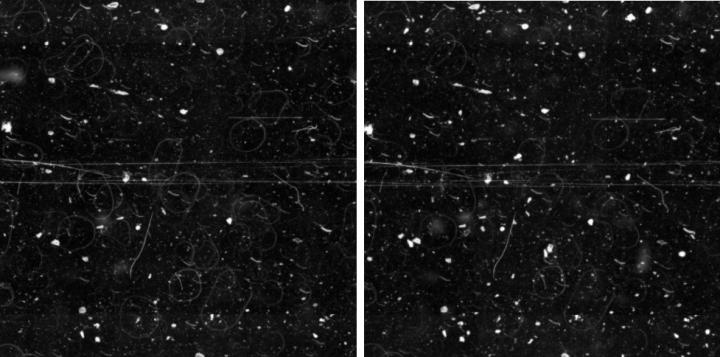

Highly Stable and Uniform SurfaceMaintains a smooth profile, crucial for consistent and reliable digital focusing. |

Image

Optimized for AI and EfficiencyCleaner scans reduce the need for rescans, saving time and enabling accurate AI analysis |

Image